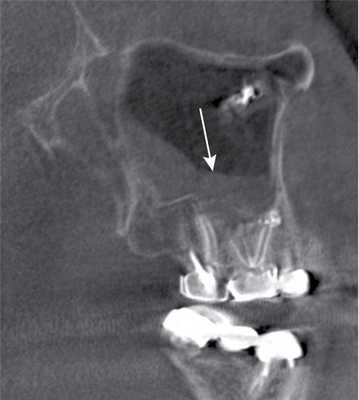

Рис. 3. КЛКТ. Сагиттальная реконструкция, правый верхнечелюстной синус. Пациент У., 48 лет. Диагноз: правосторонний одонтогенный хронический верхнечелюстной синусит. Зубы 1.6 и 1.7 после эндодонтического лечения, отмечается выведение пломбировочного материала за верхушки корней зуба 1.6 (материал располагается в костной ткани альвеолярного отростка и в подслизистом слое синуса). Определяется разрежение костной ткани в области корней 1.6 и 1.7, костная стенка синуса в данной области не прослеживается (стрелка). В нижнем отделе синуса определяется утолщение слизистой оболочки до 10 мм, в верхнемедиальном отделе синуса визуализируется инородное тело неправильной формы металлической плотности (соответствует фрагментам пломбировочного материала).